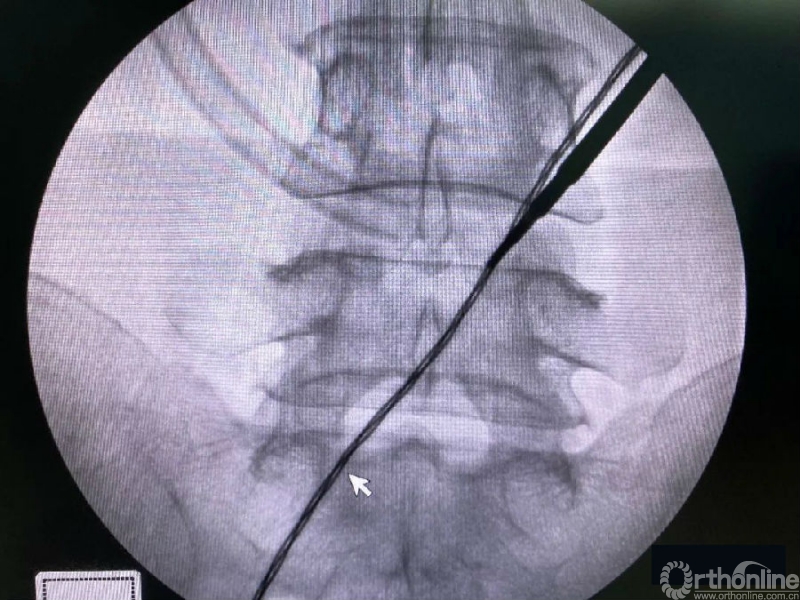

第二次定位虽然并位于椎弓根内缘线上,但是我们觉得本病历参考内缘线的话可能会把下关节突的2/3磨掉,所以我们选择第二个接近椎弓根内缘线的定位孔作为镜下下关节突内缘切除的外界。

术中第一次及第二次的两个定位孔